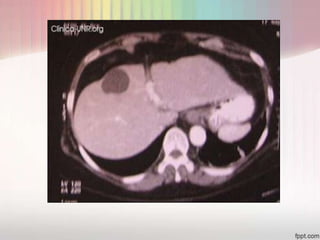

TOMOGRAFÍA      •Es la que aporta más datos precisos de tamaño y

localización de los abscesos mostrando zonas de

COMPUTARIZADA     hipodensidad

La tomografía computada muestra imágenes hipodensas, que

no captan medio de contraste y cuya densidad es líquida.

No se observan septos ni formaciones intraquísticas.